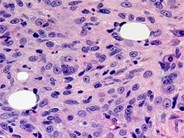

Peripheral blood smear from a patient with Acute Megakaryoblast Leukemia shows megakayroblasts (arrows) with basophilic granular appearance, pseudopod (or pseudoblebs) formation and cytoplasmic projections resembling budding atypical platelets (May-Grünwald-Giemsa stain).